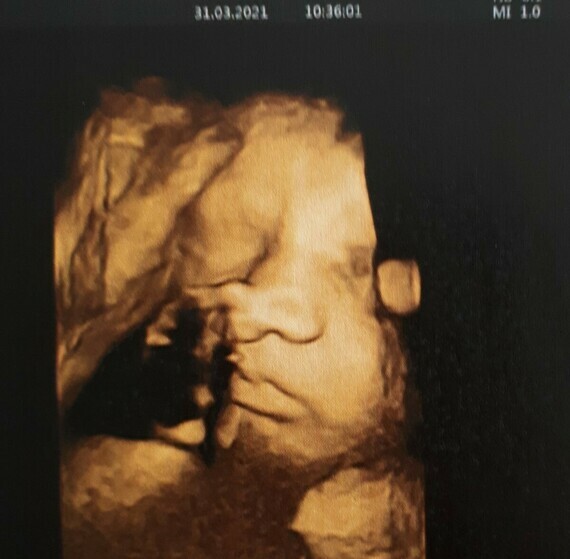

Nos Bebes En 3d A Entre 27 31sa Par Www Babycocoon3d Com Youtube

Pas Par Pas D Avoir Les 3d 4d Bebe Imageries Parfaits Youtube